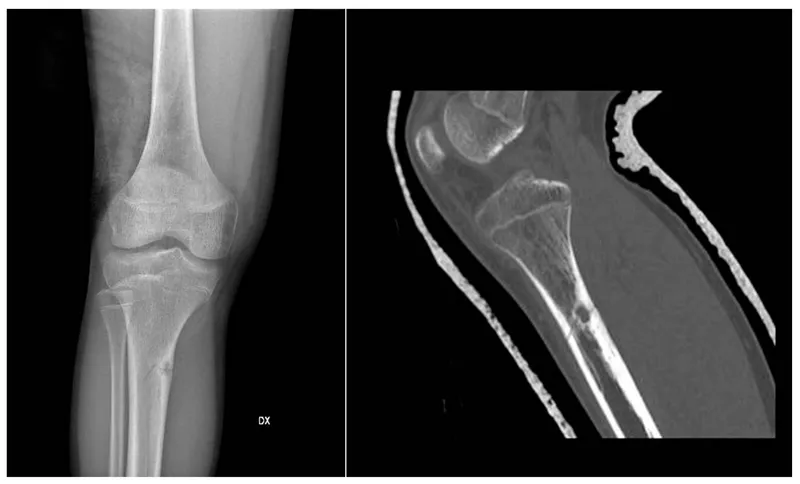

- Osteofibrous Dysplasia (OFD):

- Location: Anterior tibia/fibula cortex. Usually < 10 yrs.

- X-ray: Intracortical, lytic, often bubbly.